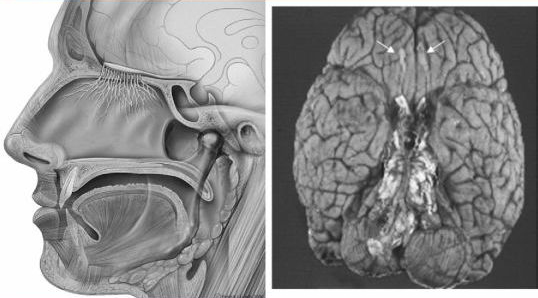

Dementia is one of the most debilitating symptoms of Parkinson's disease. A recent longitudinal study suggests that up to 80% of patients with Parkinson's disease will eventually develop dementia. Despite its clinical importance, the development of dementia is still difficult to predict at early stages. We previously identified olfactory dysfunction as one of the most important indicators of cortical hypometabolism in Parkinson's disease. In this study, we investigated the possible associations between olfactory dysfunction and the risk of developing dementia within a 3-year observation period. Forty-four patients with Parkinson's disease without dementia underwent the odour stick identification test for Japanese, memory and visuoperceptual assessments, 18F-fluorodeoxyglucose positron emission tomography scans and magnetic resonance imaging scans at baseline and 3 years later. A subgroup of patients with Parkinson's disease who exhibited severe hyposmia at baseline showed more pronounced cognitive decline at the follow-up survey. By the end of the study, 10 of 44 patients with Parkinson's disease had developed dementia, all of whom had severe hyposmia at baseline. The multivariate logistic analysis identified severe hyposmia and visuoperceptual impairment as independent risk factors for subsequent dementia within 3 years. The patients with severe hyposmia had an 18.7-fold increase in their risk of dementia for each 1 SD (2.8) decrease in the score of odour stick identification test for Japanese. We also found an association between severe hyposmia and a characteristic distribution of cerebral metabolic decline, which was identical to that of dementia associated with Parkinson's disease. Furthermore, volumetric magnetic resonance imaging analyses demonstrated close relationships between olfactory dysfunction and the atrophy of focal brain structures, including the amygdala and other limbic structures. Together, our findings suggest that brain regions related to olfactory function are closely associated with cognitive decline and that severe hyposmia is a prominent clinical feature that predicts the subsequent development of Parkinson's disease dementia.